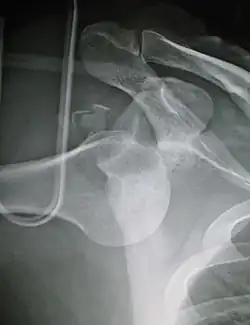

Anterior dislocation of the left shoulder.

X-ray at left shows anterior dislocation in a young man. X-ray at right shows the same shoulder after reduction and internal rotation, revealing a Bankart lesion and a Hill-Sachs lesion.

In over 95% of shoulder dislocations, the humerus is displaced anteriorly.[8] In most of those, the head of the humerus comes to rest under the coracoid process, referred to as sub-coracoid dislocation. Sub-glenoid, subclavicular, and, very rarely, intrathoracic or retroperitoneal dislocations may also occur.[9]

A Hill–Sachs lesion is an impaction of the head of the humerus left by the glenoid rim during dislocation.[6] Hill-Sachs deformities occur in 35–40% of anterior dislocations. They can be seen on a front-facing X-ray when the arm is in internal rotation.[11] Bankart lesions are disruptions of the glenoid labrum with or without an avulsion of bone fragment.[12]